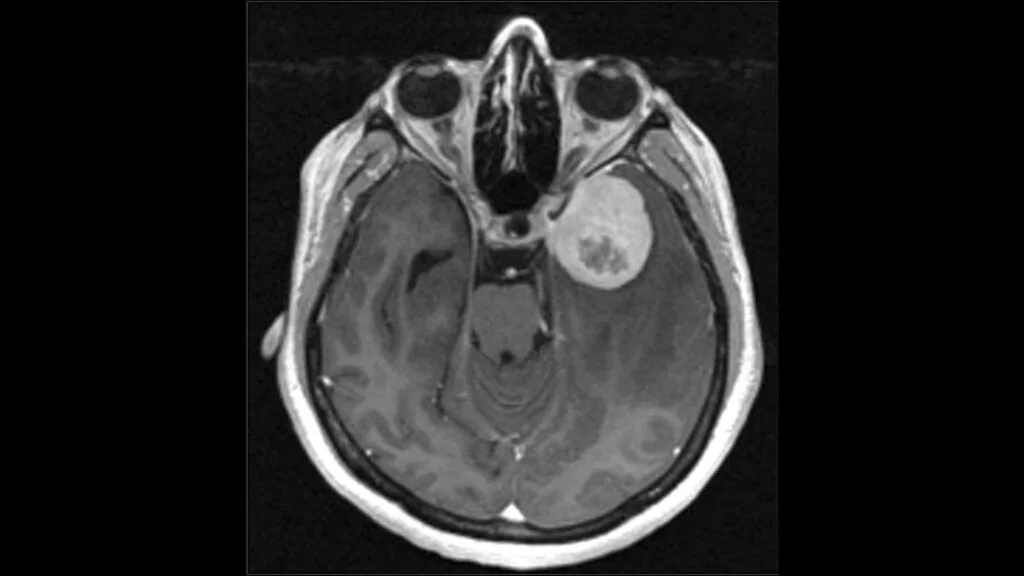

Rochester, Minggu 23 November 2025- Sebuah studi multi-institusi yang dipimpin oleh Mayo Clinic menunjukkan temuan signifikan yang dapat mengubah cara dokter mendiagnosis dan menangani meningioma, jenis tumor otak yang paling umum

Penelitian yang dipresentasikan pada konferensi Society for Neuro-Oncology (22/11) ini menemukan bahwa tumor yang menunjukkan aktivitas pada gen telomerase reverse transcriptase (TERT) cenderung kambuh lebih cepat, meskipun tampak ringan di bawah mikroskop

Meningioma umumnya dianggap jinak dan diklasifikasikan dalam tiga tingkatan berdasarkan pertumbuhan. Namun, penelitian yang menganalisis lebih dari 1.200 meningioma dari tiga negara ini menemukan bahwa tumor positif TERT-meskipun secara resmi berlevel 1- berperilaku layaknya tumor level 2